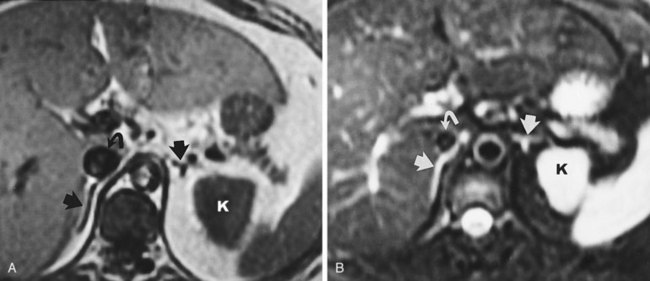

Measuring bladder wall thickness may assist the clinician in understanding the degree of bladder outlet obstruction (Fig. 4–37). Bladder wall thickness varies depending on the volume of urine in the bladder and on which part of the bladder wall is measured. It has been shown that measuring bladder wall thickness may predict bladder outlet obstruction with greater accuracy than free uroflowmetry, postvoid residual urine, and prostate volume (Oelke et al, 2007).

Figure 4–37 Bladder wall thickness may provide information about bladder outlet obstruction. In this sagittal view, bladder wall thickness is measured posteriorly (arrow) near the midline. Note the trabeculation of the relatively hyperechoic bladder wall.

Transabdominal prostatic ultrasonography requires angling the probe beneath the pubic bone. In the transverse plane the transducer is fanned inferiorly until the largest transverse diameter of the prostate is identified. Measurements of the transverse width and height are obtained (Fig. 4–38A). The transducer is then rotated 90 degrees clockwise to produce a true sagittal image of the prostate. The transducer is fanned until the midline is identified. This is recognized by a v-shaped indention at the bladder neck (Fig. 4–38B). Depending on the degree of prostatic hypertrophy and the presence or absence of a middle lobe, this “v” may be more or less apparent and more or less anterior or posterior in its position. A sagittal measurement is made from the bladder neck to the apex of the prostate. The apex of the prostate may be identified by using the hypoechoic urethra as a guide.

Figure 4–38 A, Transabdominal ultrasound is extremely useful for measuring prostatic volume and evaluating prostatic morphology. The volume of the prostate can be calculated using this formula: prostate volume (mL) = width (cm) × height (cm) × length (cm) × 0.523. B, In this midsagittal view of the prostate, the bladder neck is identified as a V-shaped indentation (arrow). Note the characteristically hyperechoic trigone (arrowhead).